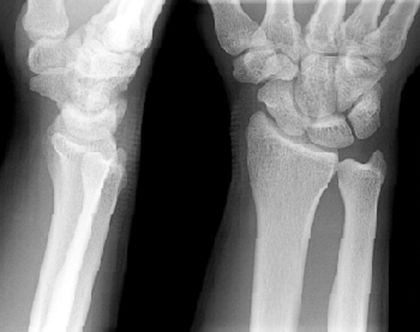

Colles骨折

桡骨远端骨折

骨折向掌侧成角

远折端向背侧移位

Smith骨折

正常腕关节